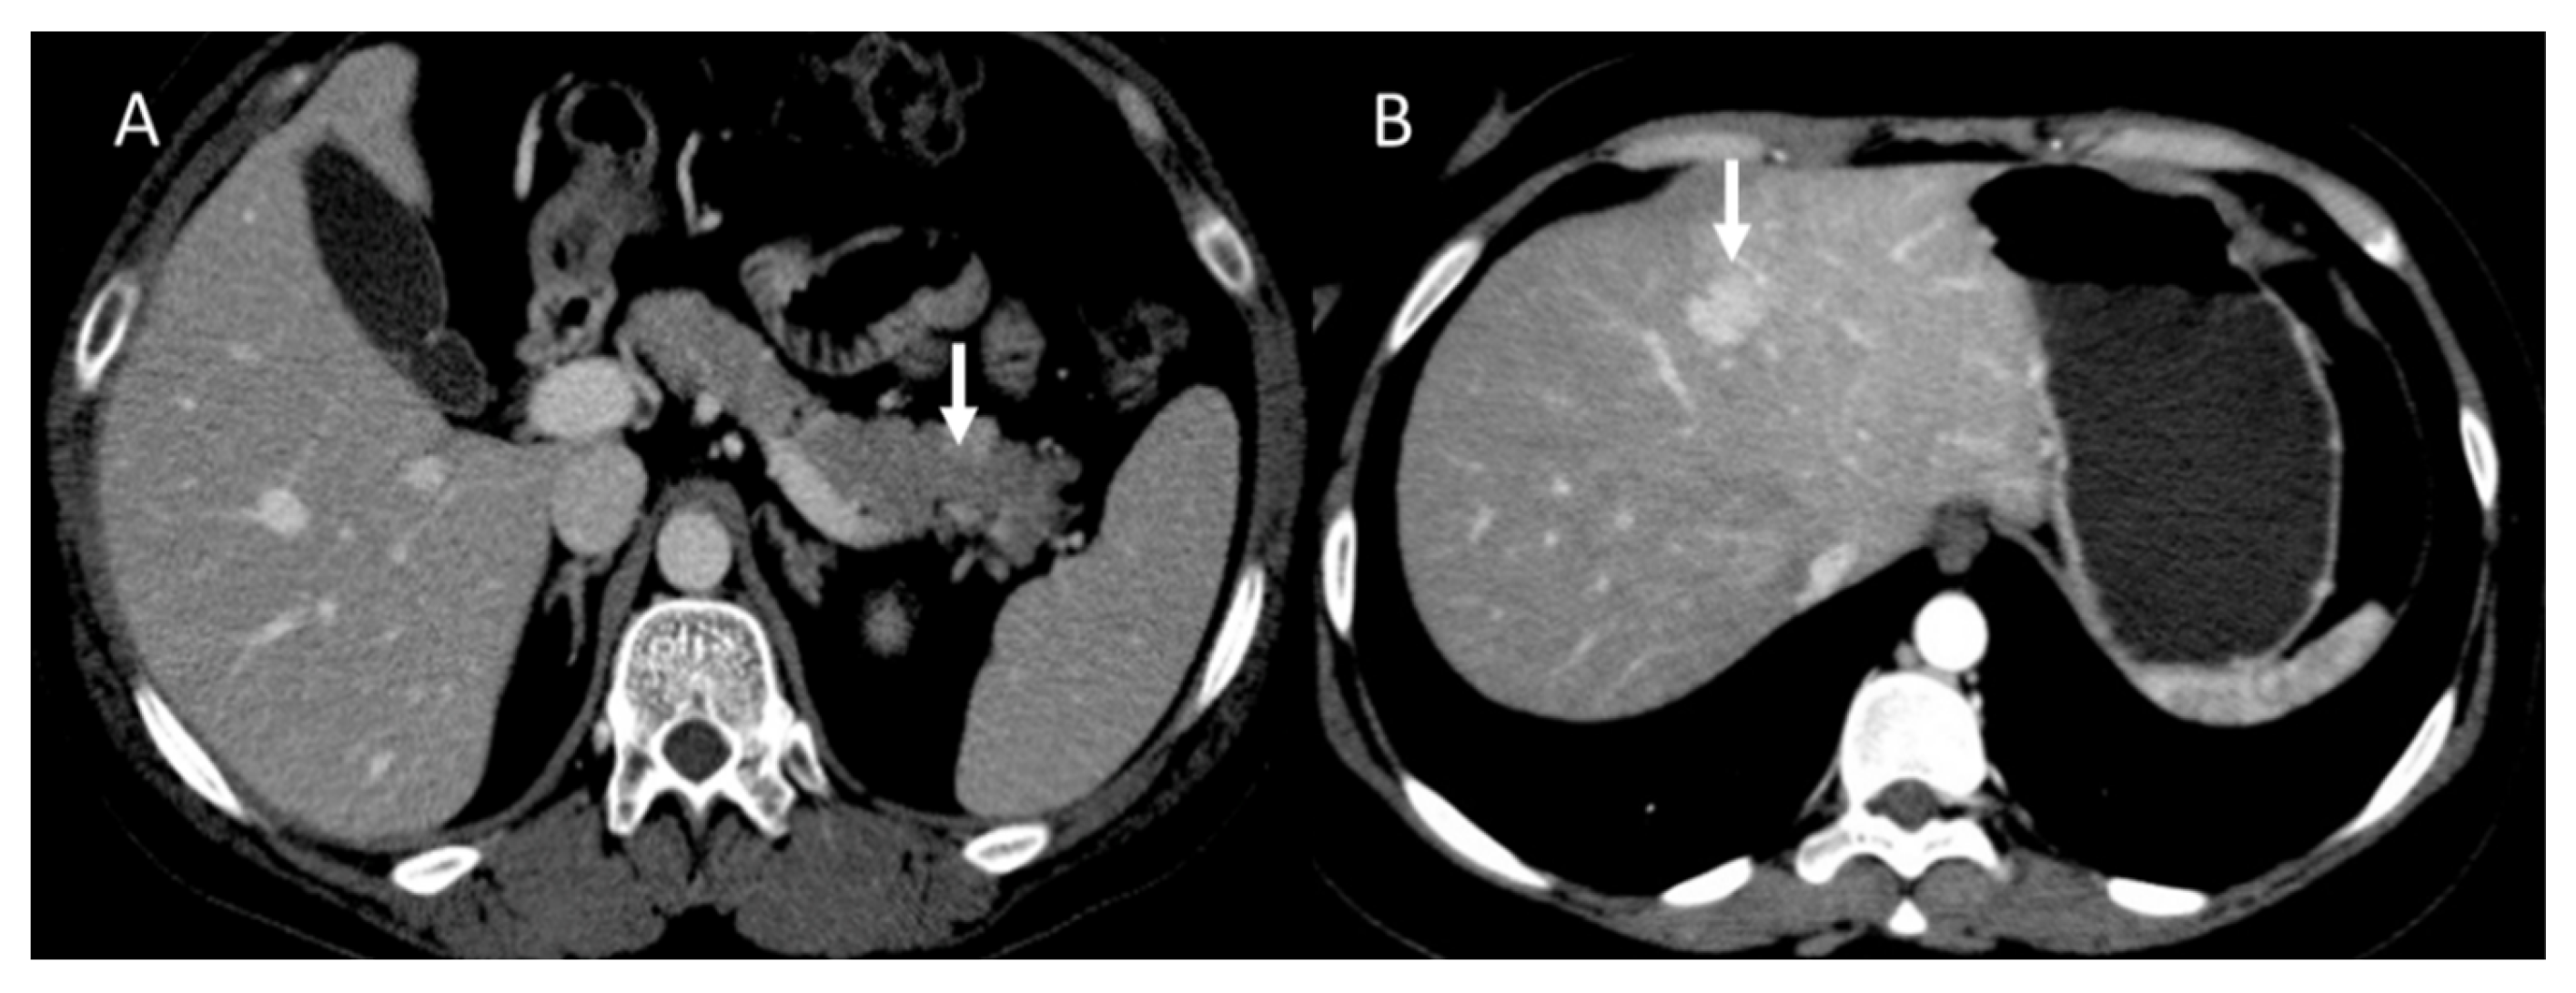

In contrast, in 68GaSSA PET/CT radiomics analysis, a higher entropy value resulted in a better association with PFS and OS, [120] in patients treated with PRRT. The entropy and kurtosis of the ADC were found to be higher in aggressive tumors, especially those with vascular invasion, lymph node disease, and liver metastases [98] (Figure 5). Although several parameters were significant for several aggressivity markers, kurtosis was found to be the best parameter in the identification of vascular invasion, showing an AUC of 0.763 using a cut-off value equal to 4.13, and in the identification of distant metastases, showing an AUC of 0.820 using a cut-off value of 3.64 [98].

Figure 5.

MRI evaluation of liver pNEN metastases. Morphological evaluation ((A): T1-W image) show hypointense lesions (arrow); in DWI ((B): b800 s/mm2), lesions show restricted signal.